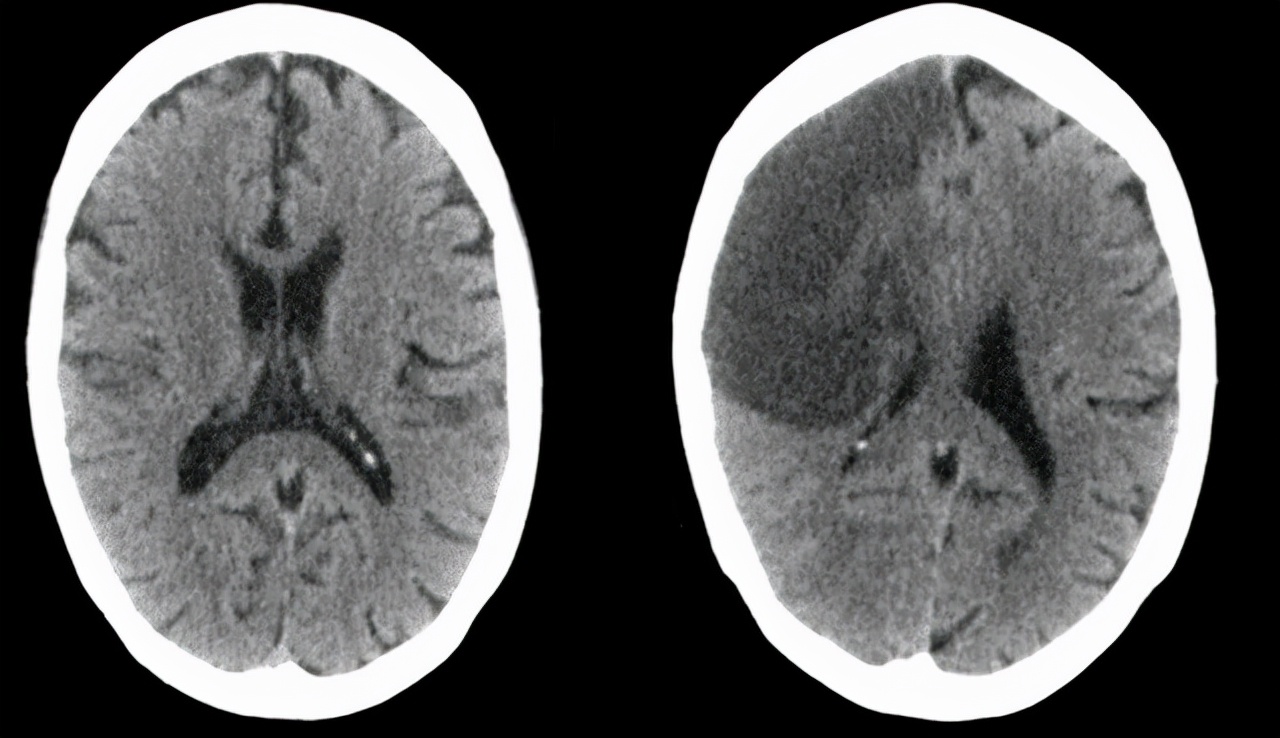

老婆瞧见马上联络120,抵达大医院后,医师马上分配查验,发觉王先生脑血管比较严重阻塞,诊断为脑梗,幸运地是送来及时,还有治愈的可能。